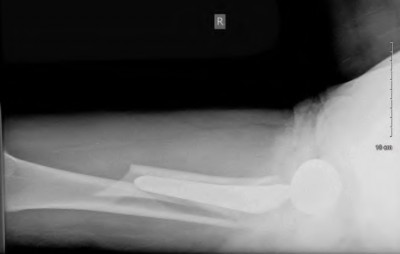

An 82-year-old woman falls and sustains the fracture shown in figure A. She denies any history of dislocation or prodromal pain prior to her fall. What is the most appropriate treatment?

The radiograph demonstrates a periprosthetic femur fracture extending to the tip of the stem. The long spiral fracture is consistent with a loose implant. The bone stock is sufficient. Therefore, this fracture pattern would classify as a B2 using the Vancouver classification system. The Vancouver classification for periprosthetic femoral fractures is simple yet incorporates all the pertinent factors such a location, stem fixation, and bone stock. Type A is a trochanteric fracture- lesser or greater. These can be treated non-operatively usually and ORIF if symptomatic. Type B fractures are around or just below the stem and are subdivided into three types. Type B1 is a fracture with a well fixed stem.

The treatment is cable plating or allograft struts or a combination of the two. Type B2 is a fracture with a loose stem with good bone stock. The treatment is a cementless porous coated long stem atleast two diameter length past the

fracture site. Type B3 is a fracture with a loose stem and comminution. For younger patients, use cementless porous coated long stems with allograft struts. For older patients, consider a tumor prosthesis. Cement fixation is sometimes necessary Type C is a fracture well below the stem tip. These can be treated independently of the prosthesis.

Springer et al showed optimal outcomes with revision involving long extensively-coated femoral stems for Vancouver B fractures.

Masri et al review the classification and treatment of periprosthetic femur fractures.

Figure A shows a lytic lesion of the proximal femur with an intramedullary implant. Figure B shows a proximal femoral replacement.